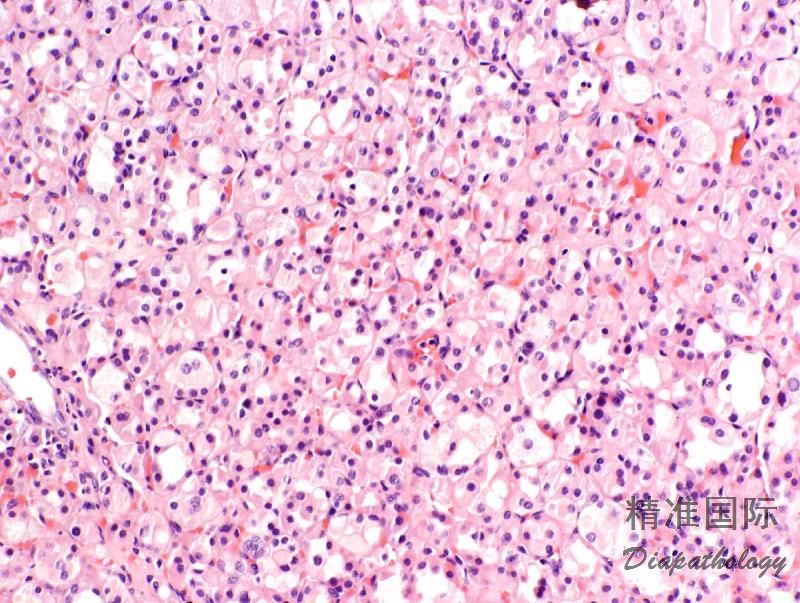

4,形态学上肿瘤一般界限较清楚部分带包膜,整体上呈分叶状或推挤状状生长,周边常见内陷的良性肾小管,常表现为不规则分支和乳头状结构。瘤细胞以实性、巢状排列为主,常见不同程度的微囊或多囊性扩张以及小管形成,偶尔可见乳头状生长结构。瘤细胞胞浆丰富,嗜酸性,SDH-RCC 最具特征性的组织学表现为胞浆内存在半透明的包涵体,内含嗜酸性或浅染的絮状物质,当这一改变显著时可造成肿瘤明显的空泡状低倍观。

5,肿瘤细胞核形态通常较温和,具有神经内分泌样的染色质,Fuhrman 核分级一般为 1 级或 2 级,偶尔可表现为高级别形态或肉瘤样转化。在高级别肿瘤中,SDH-RCC 特征性的胞浆内包涵体可能并不明显,需要广泛的取材仔细的寻找。肿瘤间质一般比较稀少,常见不同程度的水肿或出血,背景内可见较多量的肥大细胞浸润。